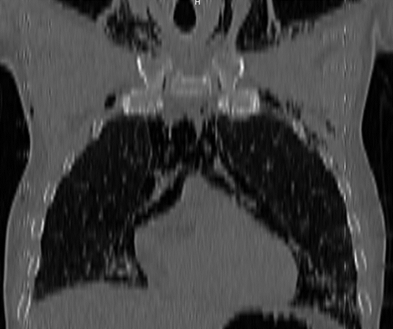

Tomografía axial computarizada de tórax: a nivel de ambos lóbulos inferiores y parcialmente en lóbulo medio derecho se observa engrosamiento de los septos interlobulillares centrales de alta densidad tomográfica e imágenes nodulares subpleurales de mediana densidad. Diagnóstico: fibrosis intersticial.

Se realizó rayos X de tórax que informó presencia de enfisema celular subcutáneo e imagen sugerente de neumomediastino (Figura 3), por lo que se indicó estudio tomográfico de tórax que informó presencia de aire en todos los compartimientos del mediastino, enfisema subcutáneo en las paredes anterior, posterior y laterales del tórax. (Figura 4).